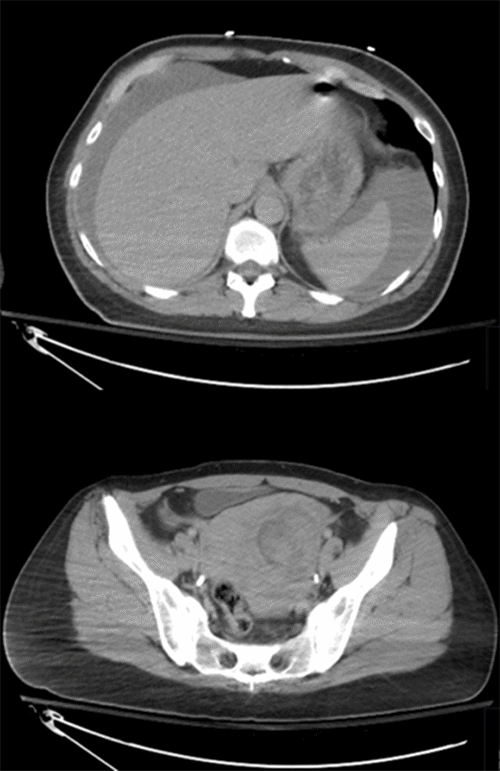

A FAST exam was positive at the outside facility prior to transfer. The patient had subsequent CT imaging with IV contrast prior to transfer. CT of the abdomen/pelvis demonstrated a large pelvic hematoma measuring 10.5 × 10.3 × 13 cm with possible adnexal origin and hemorrhagic ascites (Figure 1). No active extravasation was noted. The remaining imaging was unremarkable except for a displaced nasal spine fracture.

Figure 1. Contrast CT of Abdomen/Pelvis Demonstrating Hemorrhagic Ascites and Pelvic Hematoma. Published with Permission